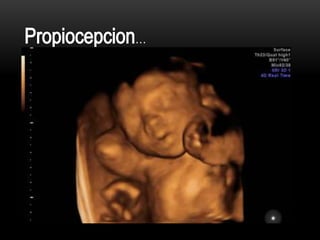

Sus sentidos están activos y la corteza cerebral ha madurado lo suficiente como para

albergar el conocimiento,

El feto ya paso mucho tiempo escuchando la voz de la madre que se ha

familiarizado con su ritmo incluso responderá a la voz de la madre

El feto ya puede oír, distinguir sabores, oler y sentir, probablemente se haya

puesto cabeza abajo para el útero y se está preparando para el momento de su nacimiento,

para la madre este cambio puede conllevar patadas bastante doloras en las costillas.